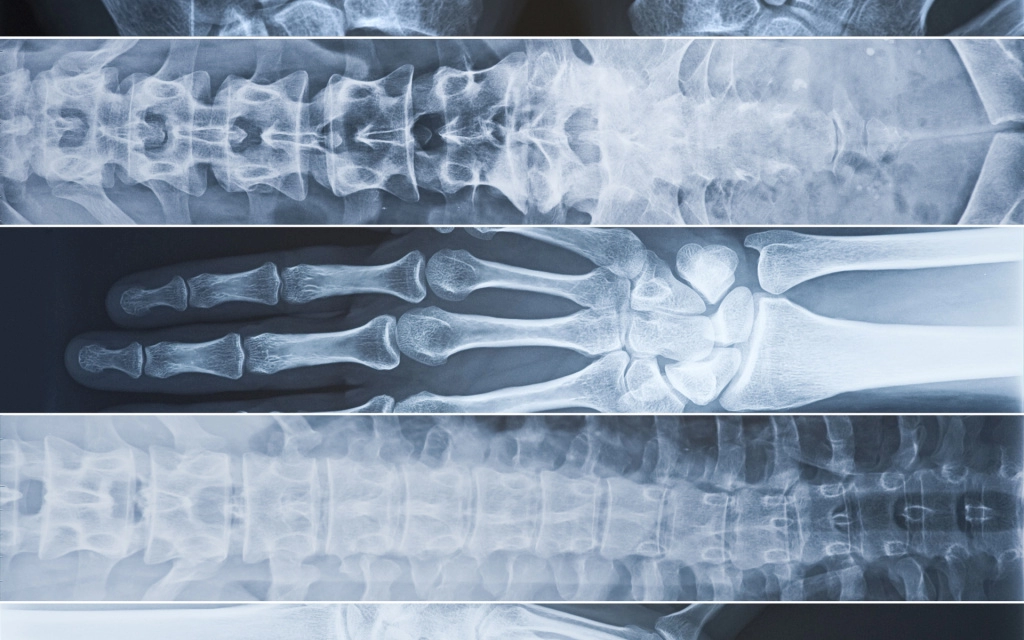

Рентгенография: быстрое и точное исследование для точного диагноза

Рентгенография – традиционная, проверенная и хорошо зарекомендовавшая себя методика обследования внутренних органов. Без нее сегодня трудно представить постановку диагноза. Рентгенография дает быстрые наглядные результаты, такое обследование эффективно и безболезненно.

• Она широко используется в травматологии и ортопедии для обнаружения переломов, деформаций и других патологий костей и суставов.

• Также рентгенография может быть полезна при обследовании органов грудной клетки, позвоночника и зубов.

Рентгенография широко используется в различных областях медицины:

• травматологи и ортопеды с ее помощью оценивают состояние костей и суставов, диагностируют воспалительные процессы, определяют наличие злокачественных образований;

• в пульмонологии качественно сделанный снимок легких позволяет диагностировать пневмонию, выявить признаки пороков развития органов дыхания и других заболеваний, своевременно обнаружить туберкулез;

• гастроэнтерологи прибегают к рентгенографии, чтобы изучить состояние желудка, в частности при подозрении на острую кишечную непроходимость, перфорацию язвы желудка и двенадцатиперстной кишки.